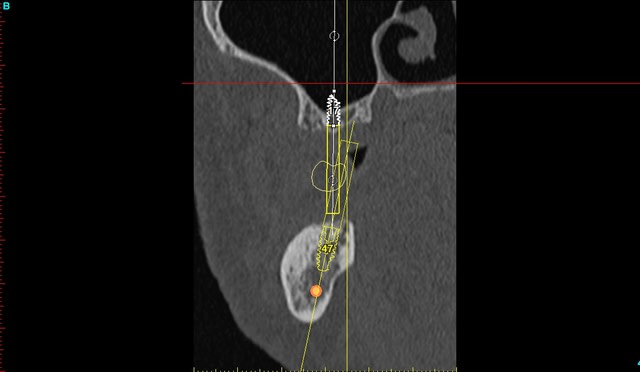

je mets les coupes et les radios post op...

intervention "quasi" flaless, juste des incisions crestales en W pour manager les papilles...

dommage j'ai oublié de prendre mes radios d'un ptit cas clinique fait vendredi...12/22 agénésies et il fallait vraiment viser juste pour éviter les racines des dents adjacentes...et être pile pour pouvoir faire les couronnes provisoires transvissées...

je ne devais pas avoir plus d'un demi mm et 1° de marge d'erreur possible pour ces 2 implants...

je posterai les images du scan et les radios post op du cas dont je viens de parler mardi ou mercredi, c'est quand même intéressant de voir ce que l'on arrive à faire avec et avoir comme précision...je n'ai presque pas décollé (petites incisions crestales en W pour aménager les futures papilles), posé les implants et réalisé les 2 couronnes prov transvissées en une petite heure seulement...